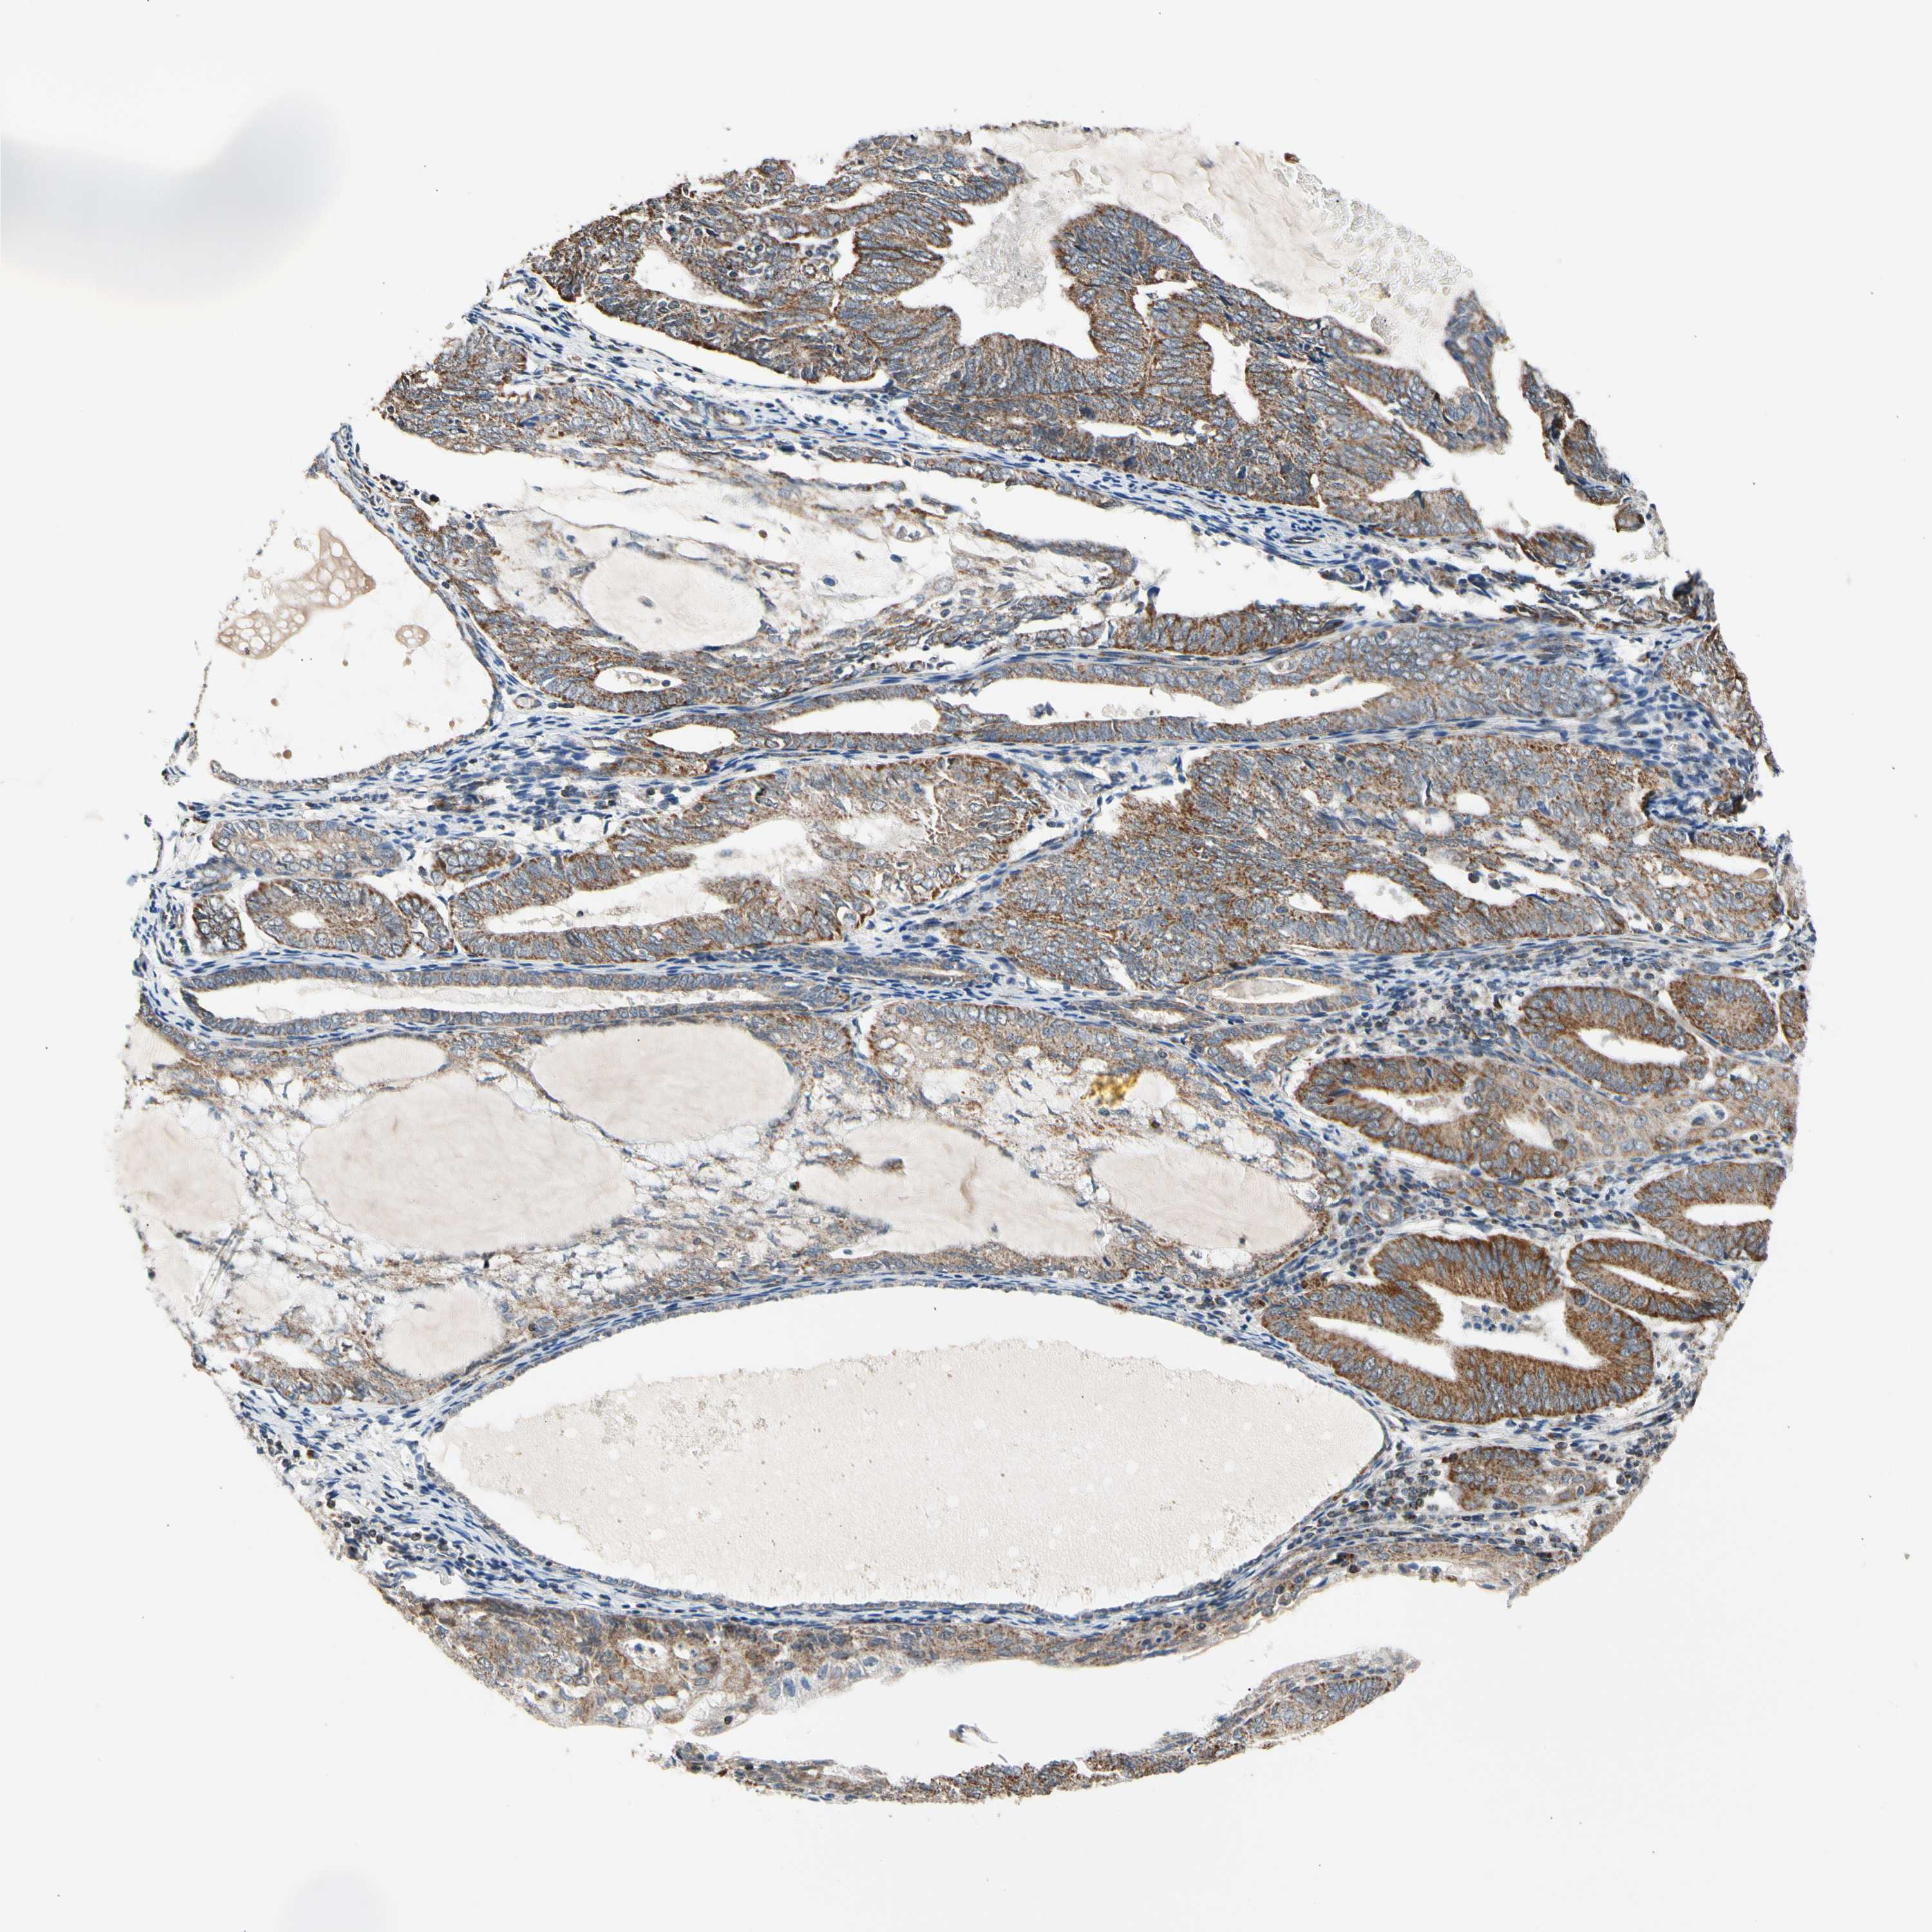

ENDOMETRIAL CANCER - Protein expressioni

A mouse-over function shows sample information and annotation data. Click on an image to view it in a full screen mode. Samples can be filtered based on level of antibody staining by selecting one or several of the following categories: high, medium, low and not detected. The assay and annotation is described here.

Note that samples used for immunohistochemistry by the Human Protein Atlas do not correspond to samples in the TCGA dataset.

Antibody stainingi

Antibody staining in the annotated cell types in the current human tissue is reported as not detected, low, medium, or high, based on conventional immunohistochemistry profiling in selected tissues. This score is based on the combination of the staining intensity and fraction of stained cells.

Each image is clickable and will lead to virtual microscopy that enables deeper exploration of all samples and also displays staining intensity scores, fraction scores and subcellular localization as well as patient and tissue information for each sample.

Antibody HPA008796

Staining

High

Medium

Low

Not detected

Intensity

Strong

Moderate

Weak

Negative

Quantity

>75%

75%-25%

<25%

None

Location

Nuclear

Cytoplasmic/membranous

Cytoplasmic/membranous,nuclear

Adenocarcinoma, NOS